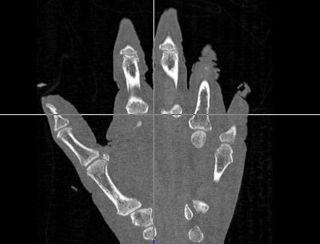

Integrate additional ITK transform types into the neural network using the general ITK transform I/O mechanism. Evaluate the changes to segment the phalanx bones bones of the hand.

- The first was that we have integrated a rigid body initialization for a Thirion Demons registration for atlas <-> subject registration. The above modification was used to warp the atlas to the subject as shown in the figures.